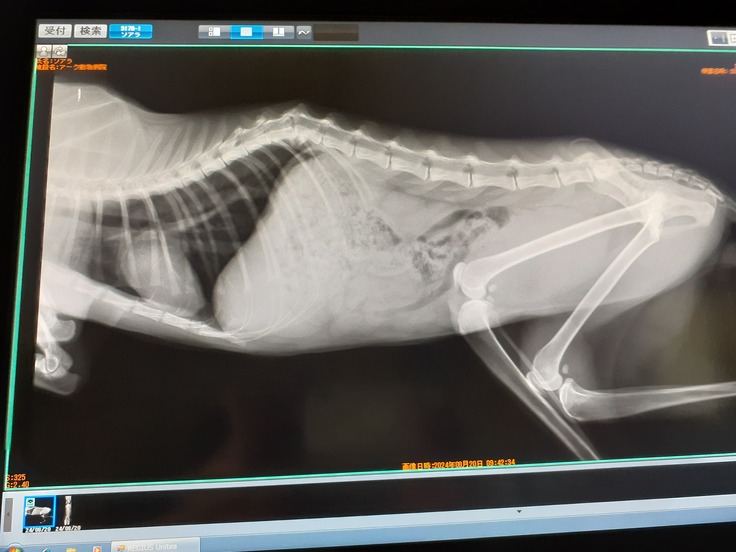

その足で動物病院にてウイルス検査、レントゲン、血液検査、便検査をしました。

レントゲンはやはり骨折。胸椎12番目が骨折をしていました。

普通に骨折ならまだ可能性はありましたが下に折れて、ズレていますのでちょっと厳しいかなと思っています。

もう固まってしまっているので元には戻らないですがそれでも希望を持って譲り受けた補助器で少しでも踏ん張る力を養えれればなと思います。